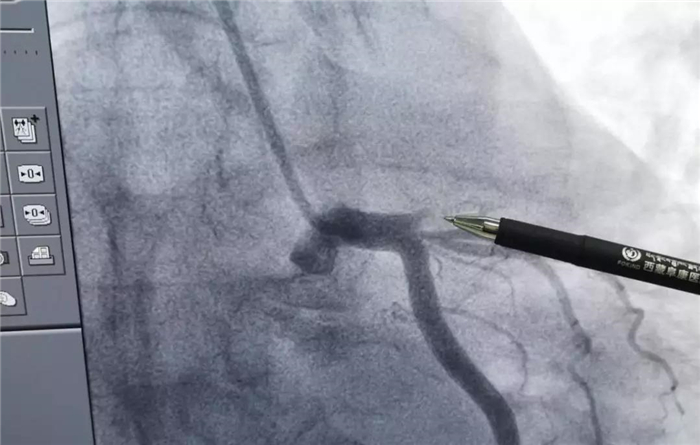

血运重建手术前

在此期间,值班医生为患者进行了抗血小板、抗凝等治疗,并完善了血常规,凝血功能,心肌酶,肌钙蛋白等检查。之后,将患者送入导管室进行冠状动脉造影检查,确诊了患者为“左冠前降支血管急性闭塞伴血栓”,由于病情凶险、危急,经过家属同意,邱耀进院长带领心血管病介入团队,立即进行了血运重建手术。